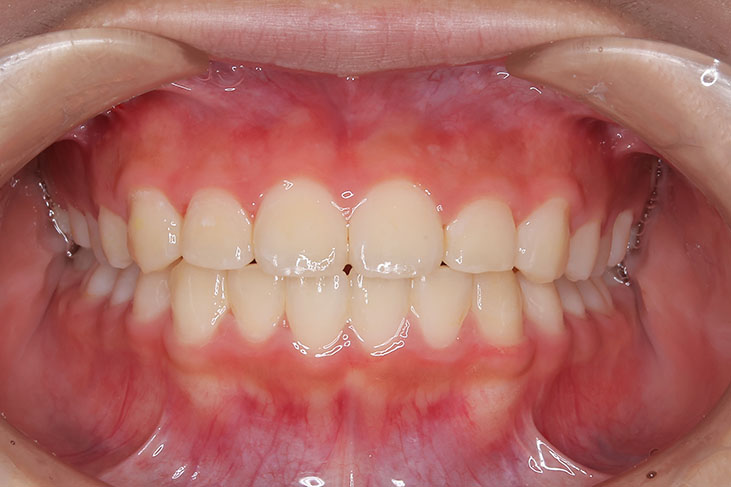

側方歯(犬歯、小臼歯)の生え変わりの時期。 前歯のがたつきを気にされ、小児矯正からの治療を希望されました。 お母様は、矯正治療経験済みですので、治療には前向きで早期治療の必要性を納得されていました。 小児矯正では、永久歯の生え変わるためのスペースを増加させ、がたつきを軽減させることを目的で行います。 残ったがたつきは、全ての永久歯が生え変わってから、本格矯正(マルチブラケット装置での治療)で改善しています。 比較的、叢生量は少ないため、本格矯正は非抜歯にて配列しました。

マルチブラケット 動的治療期間 2年6か月 調整回数16回 特に問題もなく、保定後も安定しています。